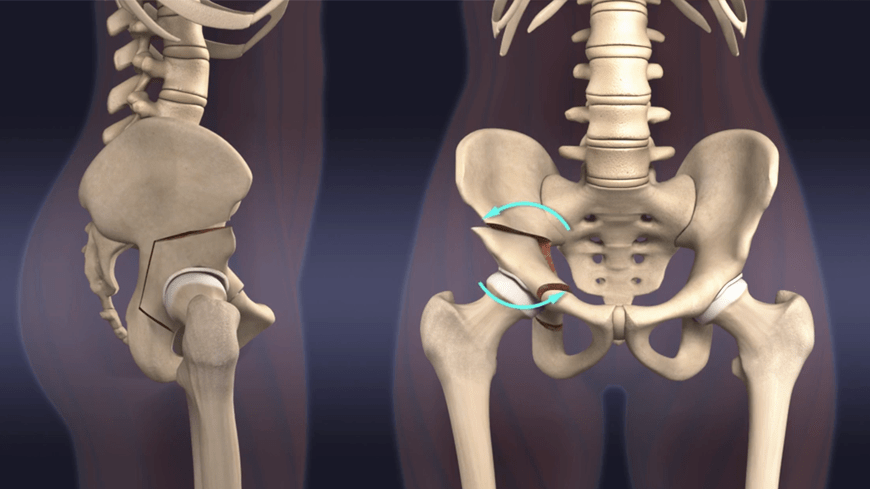

髋臼周围截骨术 髋臼周围截骨术主要针对髋关节发育不良的患者 , 不少患者儿时没有感觉 , 成年后发病 。